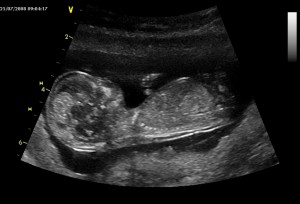

První dvě fotky jsou z 25.7., to byla maminka na začátku 14 týdne těhotenství. Tady jsem vidět ještě krásně, skoro celý, v levo hlavička a pak bříško a malá ručička. Na druhé fotce je jen detail mé hlavičky z profilu, jak si cucám paleček.